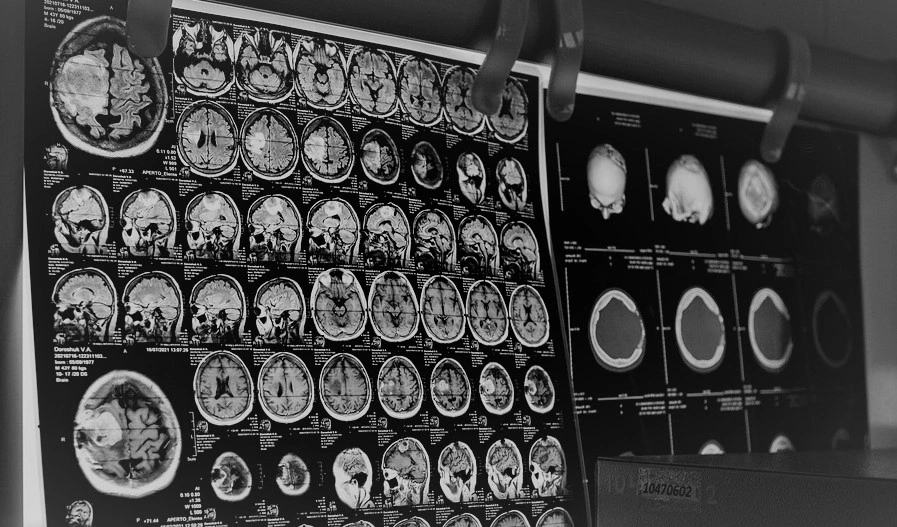

Zajęcia mają charakter praktyczny – uczestnicy poznają działanie algorytmów AI, m.in. duże modele językowe, semantyczne modelowanie danych, zastosowanie obrazowania medycznego, boty, blockchain i smart contracty w medycynie. Dodatkowo przewidziano wizytę studyjną w szpitalu, gdzie uczestnicy będą mogli zobaczyć działanie robotów w ekosystemie medycznym.